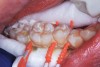

Interproximal insertion of SDF is demonstrated in different patients in Figure 3 through Figure 11. Various diameters and brands of soft dental picks may be used depending on the closeness of the proximal surfaces and ease of insertion; for example, some picks are designed for use in wider spaces between teeth. This protocol also offers versatility. Figure 3, for example, shows the simultaneous use of three thin soft dental picks to saturate proximal surfaces with SDF in a teenaged patient; the treated regions were subsequently covered with fluoride varnish (Figure 4). This patient was initially treated in April 2019 (Figure 5), with an identical re-application 3 months later. As shown in Figure 6, the December 2019 bitewing film revealed good results with the possible exception of the contact regions of the maxillary first and second molars. New SDF application was completed in the December appointment.

Figure 7 illustrates the use of thicker picks in premolar interproximal sites. Additionally, multiple picks can be used in one quadrant or in one proximal site with good isolation to maximize fluid saturation (Figure 9), which the authors have found to be an excellent time-saving strategy. Preventive or interceptive applications of SDF may also be effectively used in interproximal sites in orthodontic patients (Figure 10).

Fig 3. Three thin soft dental picks were used simultaneously for SDF proximal surface saturations in a teenaged patient (Fig 3). After 60 seconds, the treated regions were covered with 5% fluoride varnish (Fig 4). A comparison can be seen of pre-SDF-treatment bitewing films (Fig 5) and 8-month post-SDF bitewing films (Fig 6) for the patient shown in Fig 3 and Fig 4. Radiolucencies were similar or improved, except for contact of maxillary first and second molars.

Fig 5. Three thin soft dental picks were used simultaneously for SDF proximal surface saturations in a teenaged patient (Fig 3). After 60 seconds, the treated regions were covered with 5% fluoride varnish (Fig 4). A comparison can be seen of pre-SDF-treatment bitewing films (Fig 5) and 8-month post-SDF bitewing films (Fig 6) for the patient shown in Fig 3 and Fig 4. Radiolucencies were similar or improved, except for contact of maxillary first and second molars.

Figure 5